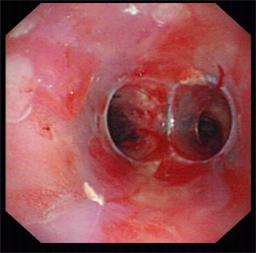

近日我科为一食道癌晚期、食道气道瘘的患者成功放置硅酮支架,患者在禁食1月后终于再次尝到了香甜的米饭,激动万分。该患者1年前在外院确诊为食道癌晚期,一直在我院放化疗科进行化疗及放疗,后患者逐渐出现进食后呛咳,复查胸部CT提示食道癌气道广泛侵袭,存在气道食道瘘可能。患者为避免进食后呛咳,已留置鼻饲,禁食1月。经我科俞万钧副院长会诊,决定为患者进行气道硅酮支架置入堵瘘口,让患者恢复进食。硅酮支架堵瘘术目前国际上开展不多,国内更是寥寥无几,手术难度大,成功率低。手术当日,俞万钧副院长亲自主刀,首先对气道浸润的肿瘤进行消融处理,后成功放置Y型硅酮支架,封堵瘘口。术后次日,患者就能进食流质,再次体会到进食的快乐。利用Y型气道硅酮支架封堵瘘口,全省目前未见报道,全国只有天坛医院,厦门二院等几家医院实施过,这一手术标志着我院硬镜,硅酮支架放置技术达到全国领先水平。(徐涛)

图片4 硅酮支架帮助重建气道